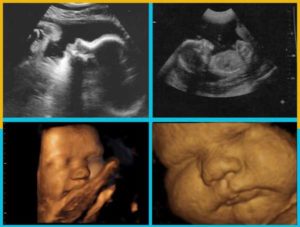

Развитие плода

На 40 акушерской неделе вес плода равен 3200-3600 г, рост – 52-55 см. На этом сроке малыш прибавляет не более 200 г веса и 1 см роста в неделю. Увеличение размеров плода практически не сказывается на весе женщины. Напротив, на этом сроке многие будущие мамы теряют до 2-3 кг за счет потери жидкости и выхода балластных веществ из кишечника.

Доношенный новорожденный имеет тонкую бледно-розовую кожу, покрытую небольшим количеством сыровидной смазки. Пушковые волосы сохраняются лишь на отдельных участках тела. Хорошо выражен слой подкожно-жировой клетчатки, особенно на животе, ягодицах и в местах естественных складок. Между податливыми костями черепа располагаются два открытых родничка – большой и малый.

На 40 неделе беременности малыш считается полностью готовым к своему рождению. В легких накопилось достаточное количество сурфактанта – важного вещества, без которого невозможно самостоятельное дыхание. Организм готовится к запуску малого круга кровообращения. В надпочечниках продолжается синтез кортизола – гормона, ответственного за запуск родовой деятельности.

Ближе к дате родов движения малыша становятся менее активными. Ребенку тесно в матке, и нет никакой возможности перевернуться или как следует пошевелить руками и ногами. Время от времени ребенок дает о себе знать сильными, но не слишком размашистыми шевелениями. Если малыш затихает на длительное время, необходимо срочно обратиться к врачу.В плаценте на 40 неделе запускаются процессы старения. Образуются очаги некроза, нарушается кровоснабжение по мелким сосудам. Ребенок, находящийся в материнской утробе, испытывает кислородное голодание.